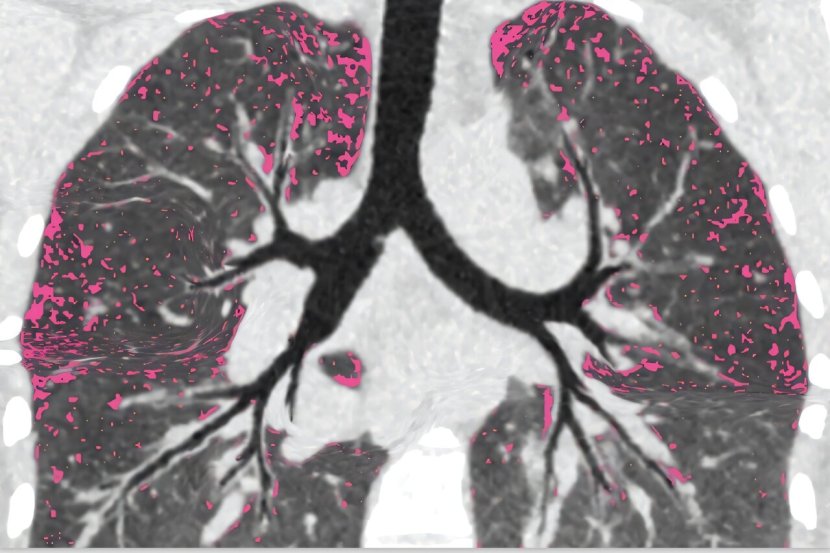

Pre nego što su učesnici studije počeli sa modulatorima, istraživači su ušli u pluća pacijenata tankim kamerama - bronhoskopima. Uzeli su uzorke iz regiona koji su se razlikovali po količini oštećenja, infekcije i upale. Zatim su ponovo ušli u iste plućne oblasti godinu dana nakon lečenja kako bi videli gde je infekcija ostala i koje karakteristike pluća imaju veze sa perzistentnom infekcijom.

- Vodeća ideja u ovoj oblasti je da pacijenti ostaju inficirani jer jako oštećeni plućni regioni ne mogu da se oslobode infekcije, slično kao što se oštećena tkiva u ranama inficiraju. Ako je sličan proces odgovoran za stalne infekcije pluća izazvane cističnom fibrozom, istraživanje može da se  fokusira na ove oblasti - naglašava dr Sid Kapnadak, pulmolog sa , koji je vodio uzorkovanje pluća za studiju.

Kada su infekcije nestale, upala pluća je skoro potpuno nestala

- Ono što smo otkrili bilo je iznenađenje, i bilo je dobrih i ne tako dobrih vesti. Dobra vest je bila da, kada su infekcije nestale, upala plućaje skoro potpuno nestala. Stoga, buduće oštećenje pluća moglo bi da bude smanjeno kod ljudi koji su se oporavili. Međutim, ljudi koji su ostali inficirani imali su infekciju i upalu svuda gde smo gledali, uključujući i područja pluća sa vrlo malo oštećenja - objasnila je dr Durfey navodeći da nalazi ukazuju na to da oštećenje pluća možda nije glavni uzrok perzistencije infekcije, ali i da izazivaju zabrinutost da bi funkcija pluća kod ljudi sa bakterijskom infekcijom mogla da nastavi da se pogoršava.